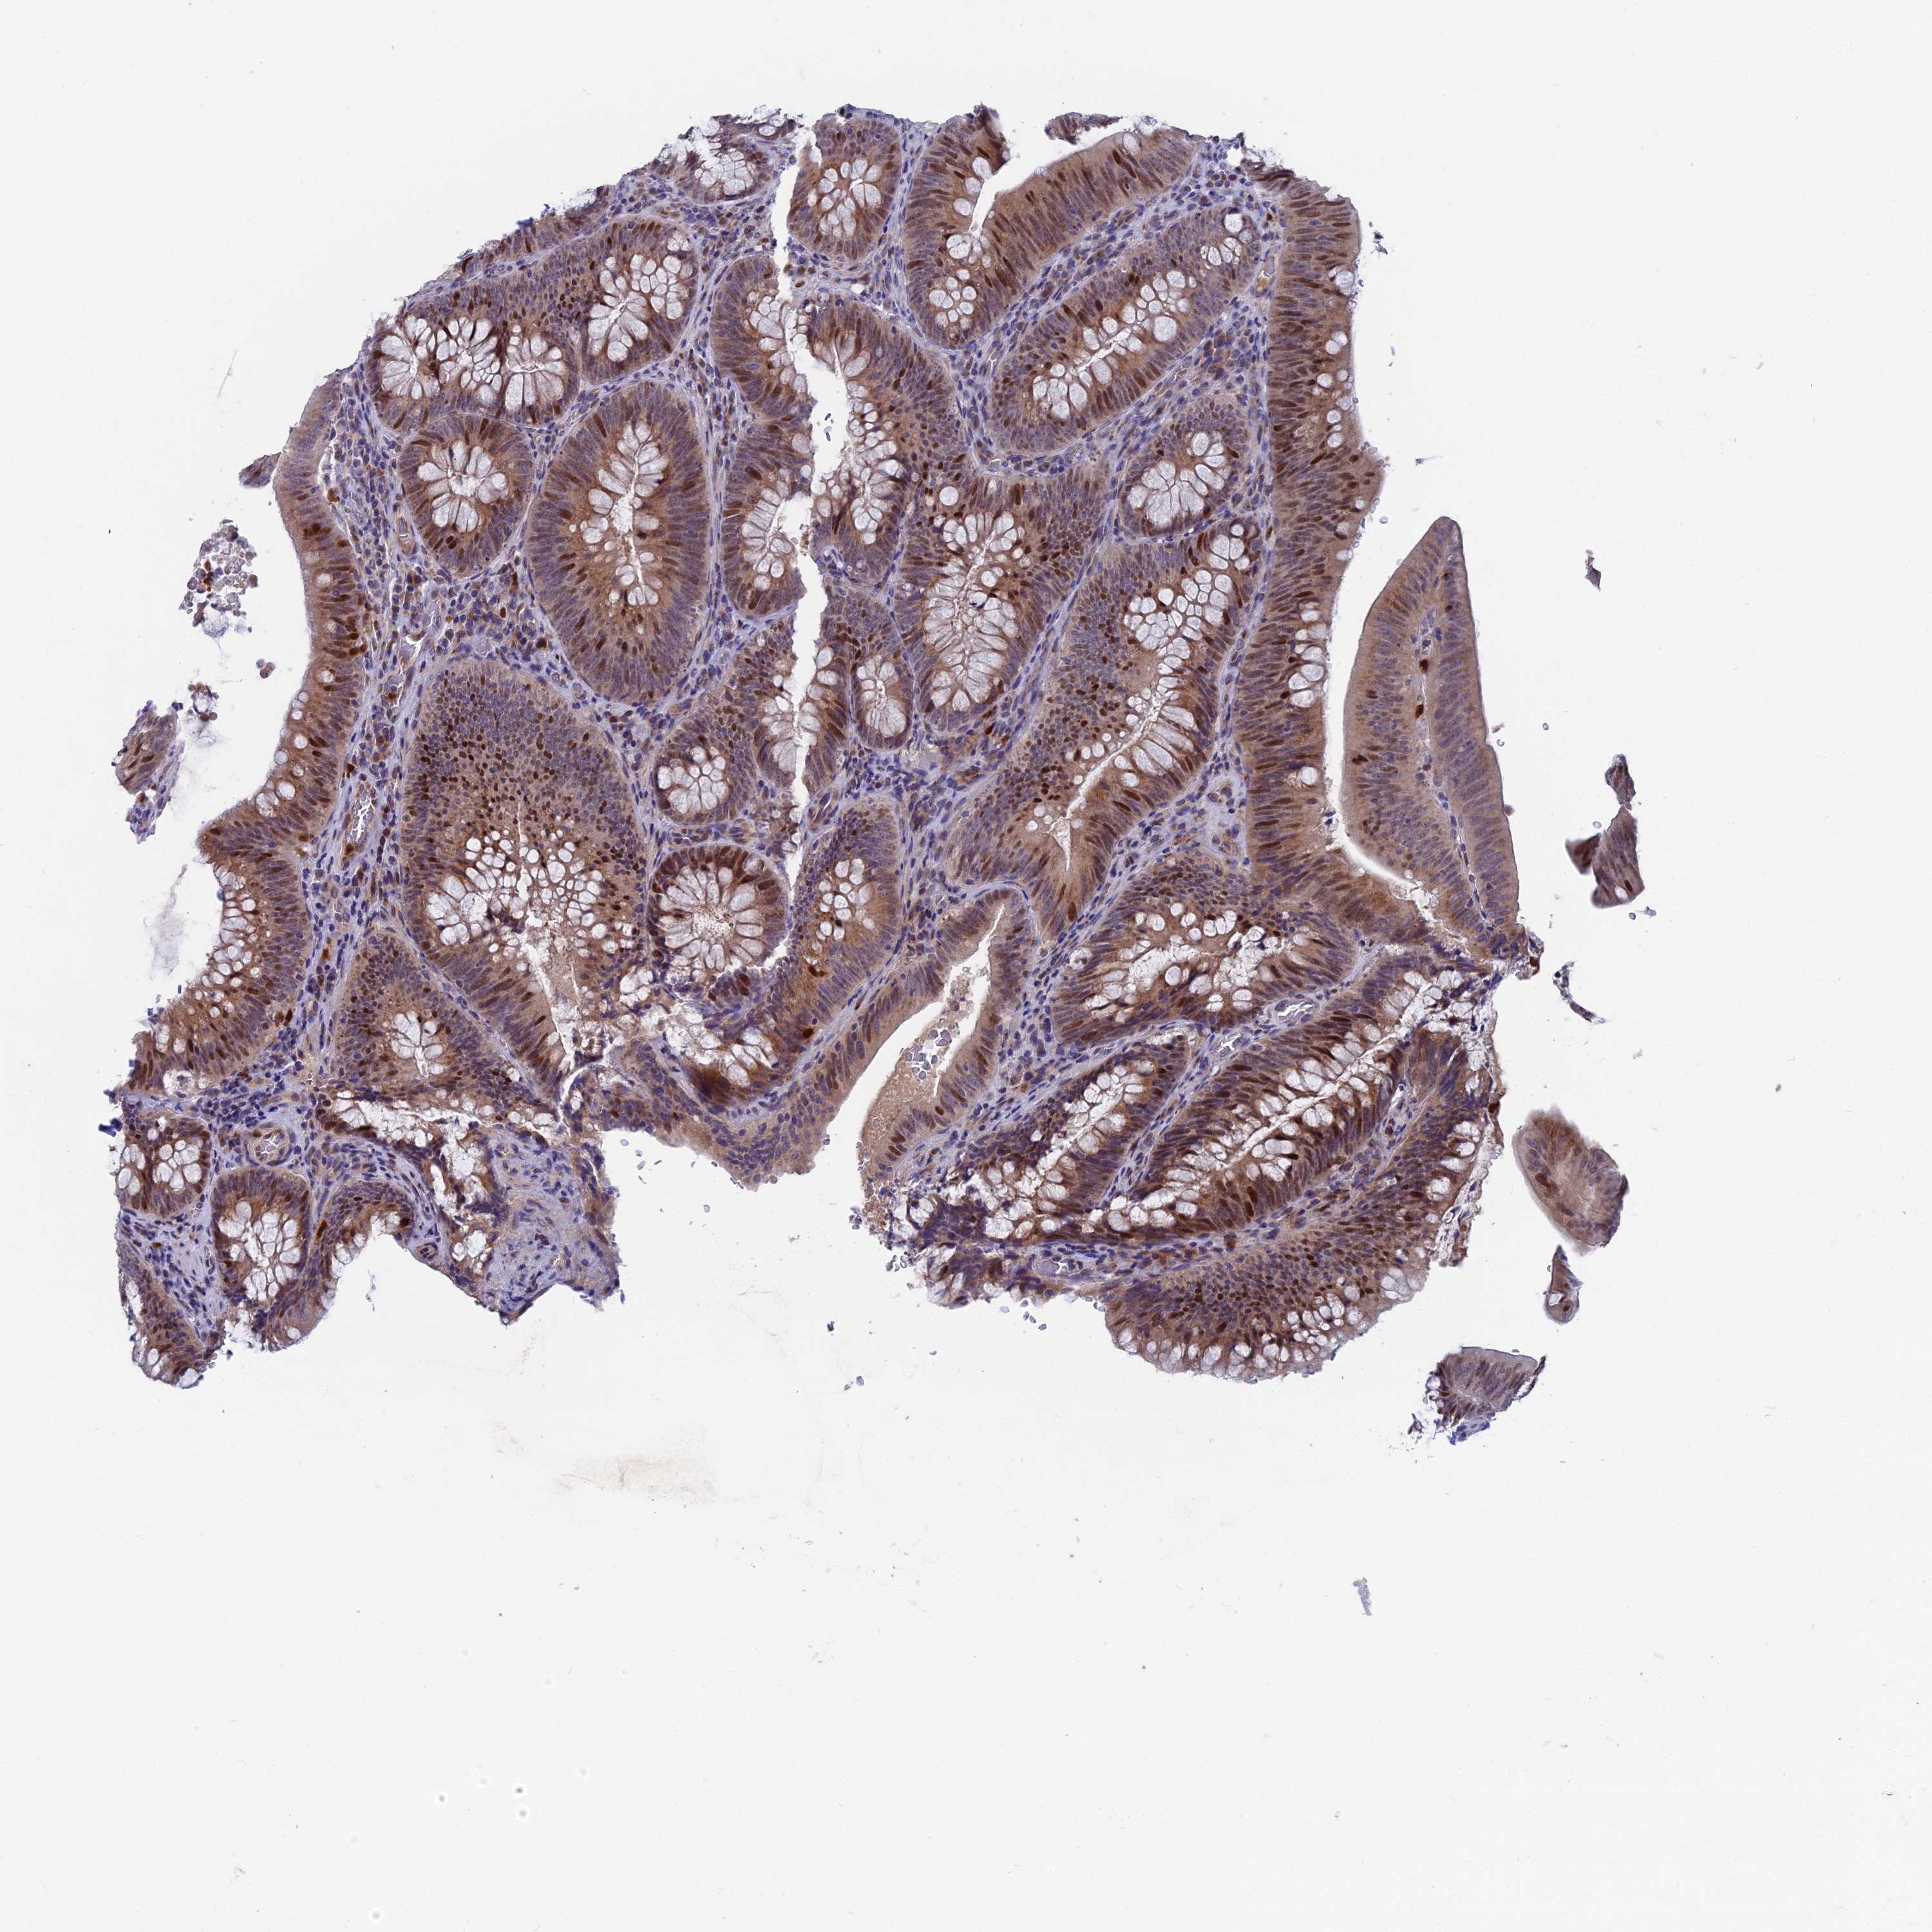

CANCER COLORECTAL CANCER Show tissue menu

Colorectal cancer

Human cancer

Colon adenocarcinoma